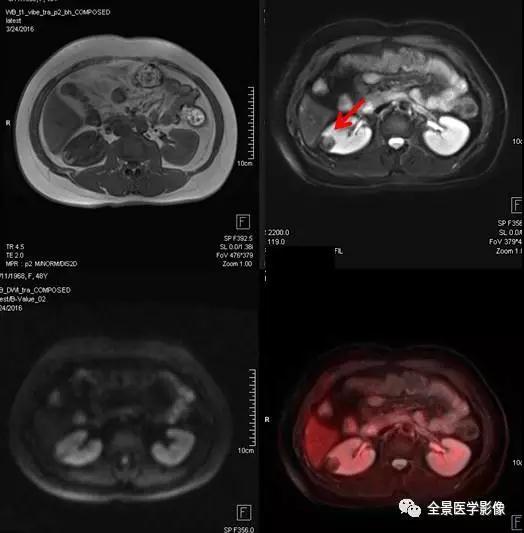

PET/MRI

泌尿系统

肾癌

◆ 案例:老年女性,右下肢胀半年余,右侧卵巢良性肿瘤术后。右肾上部见一长径约 4.5 cm 肿块,FDG 呈本底摄取。手术病理提示肾癌。

点评:

肾癌约占成人恶性肿瘤的 2%~3%,近年来,约 50% 的肾癌是经健康查体时发现的无症状肾癌。有症状的肾癌患者中最常见的症状是腰痛和血尿。对早期肾癌患者可采用微创的保肾手术,对中晚期肾癌患者则采用根治性肾切除术,因此早期发现非常重要。

血管平滑肌脂肪瘤

◆ 案例:中年女性,甲状腺肿瘤术后复查。右肾中部见直径约 2.5 cm 异常信号灶,内含脂肪信号,FDG 无代谢,诊断为血管平滑肌脂肪瘤。

血管平滑肌脂肪瘤 (以往称错构瘤) 是肾良性肿瘤中最常见者,约占肾肿瘤的 3%。肿瘤较小者,可以 B 超定期随访复查; 巨大的肿瘤会压迫邻近脏器,且容易发生出血,引起腹痛等急症,应避免剧烈运动及外伤。